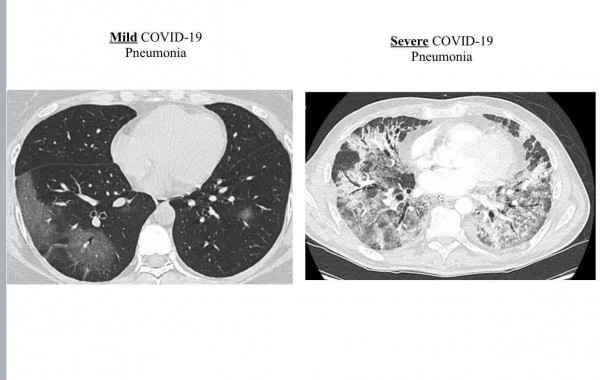

첫째 포인트: 코로나 백신은 감염예방과 함께, 중증도를 낮추는 매우 중요한 효능 지닌다고 강조한 김태형 (생명과학/생명정보학/테라젠바이오)연구원은 페이스북을 통해 신종 코로나바이러스 ‘경증’환자의 폐와 코로나 ‘중증’감염 환자의 폐를 비교한 환자들의 폐 CT 스캔 이미지를 공개하며 중증도를 낮추는 백신 효과의 중요성을 환기 시켰다.

아래 두 사진은 코로나 감염된 환자들의 폐 CT 스캔 이미지

김태형 연구원은 “왼쪽은 ‘경증’환자의 폐고 오른쪽 사진은 코로나 ‘중증’감염 환자 폐”라면서, “전 세계가 다양한 백신을 응급승인하고 1억 명 이상 백신 접종을 진행했는데 백신 접종후 COVID-19에 감염되더라도 환자들의 폐는 거의 대부분 왼쪽 사진과 같았다...말로만 듣던 백신의 효과를 이렇게 직접 눈으로 보니 정말 대단한것 같다...코로나 백신은 감염 예방도 중요하지만 이처럼 중증도를 낮추는 것도 매우 중요한듯 하다”면서, 중증도를 낮추는 백신 효과의 중요성을 환기 시켰다.